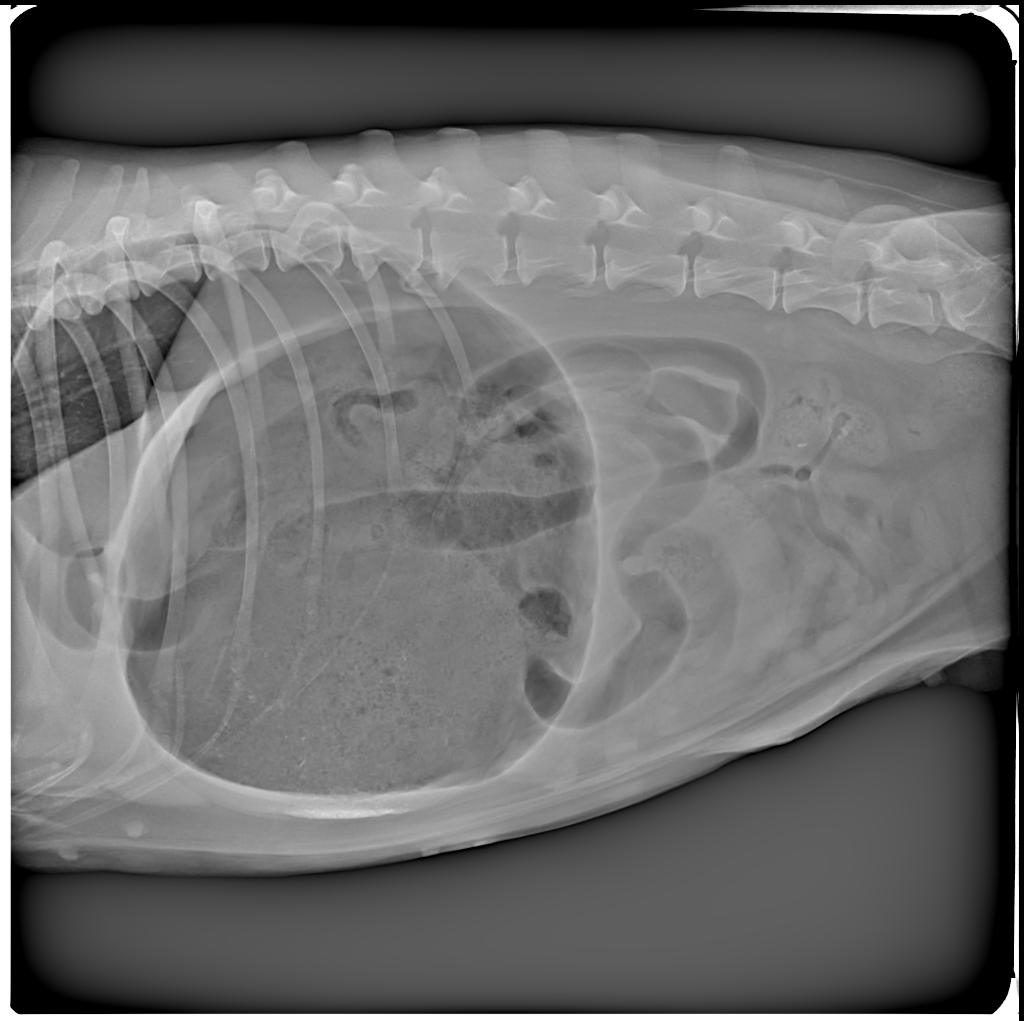

La mia cagnolina ha iniziato ad avere sintomi di “falso” vomito più o meno in orario serale. All’inizio pensavo avesse ingerito qualcosa di critico e mi sono impegnato ancora di più per cercare di farla vomitare. Ho notato però che il cane non smetteva e nei tentativi continui di vomito non “buttava fuori” niente. Il cane era nervoso, girellava per casa e non trovava pace. Il respiro si era fatto consistente e la salivazione anche. Pensando più a un avvelenamento o a un corpo estraneo ingerito, sono andato immediatamente dal veterinario che mi ha diagnosticato un caso di torsione-dilatazione gastrica.

La sindrome della dilatazione-torsione gastrica, La dilatazione-torsione gastrica, Torsione dello stomaco nel cane, Sindrome della torsione gastrica nel cane, La Torsione Dilatazione gastrica (GDV) nel cane, Dilatazione e torsione gastrica, Dilatazione e torsione gastrica nel cane